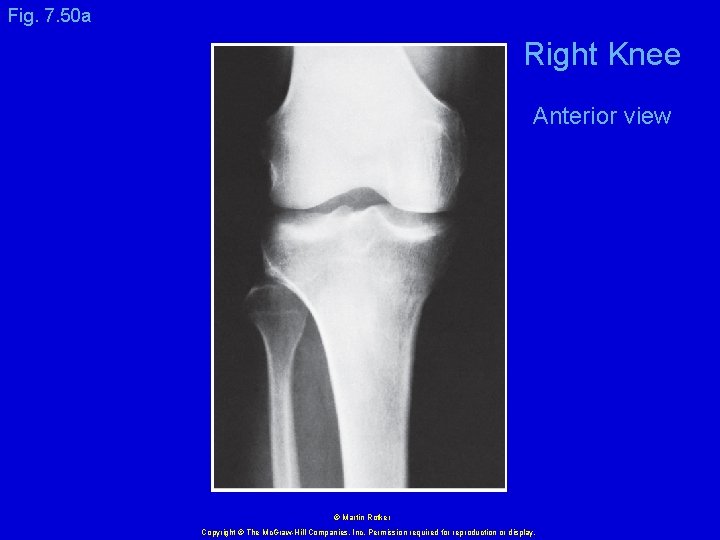

Fig. 7. 50 a Right Knee Anterior view © Martin Rotker Copyright © The Mc. Graw-Hill Companies, Inc. Permission required for reproduction or display.